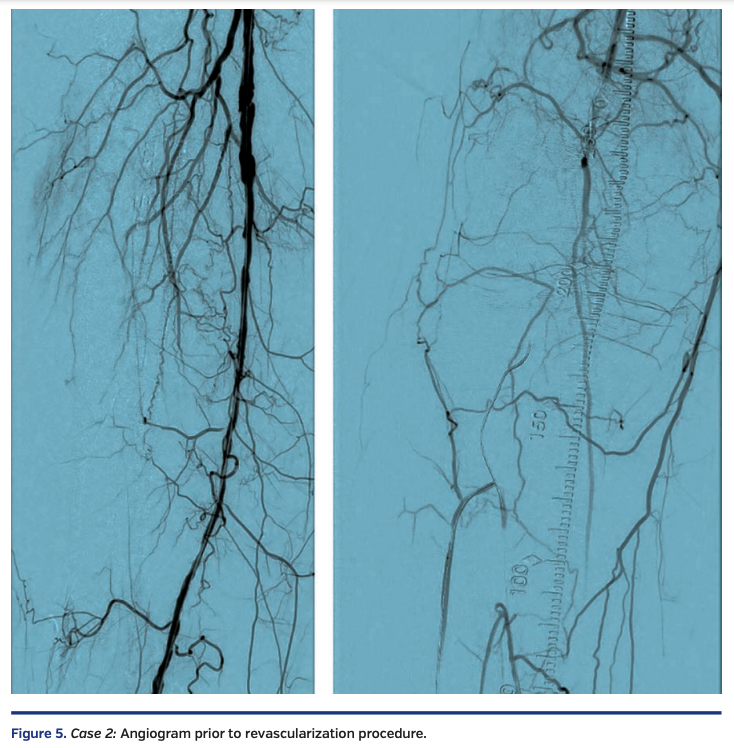

A functional white female in her late eighties with history of type 2 diabetes, hypertension, and hyperlipidemia presented with progressive right hallux discoloration and early pre-gangrenous changes over a 2-month period. Arterial duplex suggested a right popliteal artery (P3 segment) occlusion, distal posterior tibial artery occlusion, and patent anterior tibial and peroneal arteries. Diagnostic angiography, performed through antegrade access into the right common femoral artery, revealed a diffusely diseased right superficial femoral artery (SFA) and occluded P2 and P3 segment popliteal artery, with 3-vessel tibial vessel reconstitution by collaterals (Figure 5).

Sequential balloon angioplasty in the anterior tibial artery was performed with 2.0 mm and 4.0 mm Coyote balloon (Boston Scientific). Kissing balloon angioplasty of the popliteal artery, proximal anterior tibial, and tibioperoneal trunks was performed with long 3 mm balloons, followed by drug-coated balloon angioplasty of the right femoropopliteal segment with a 6 mm x 250 mm IN.PACT Admiral drug-coated balloon (Medtronic). There was restoration of normal flow in all treated segments (Figure 8), with a warm foot and a palpable dorsalis pedis artery at the end of the case.